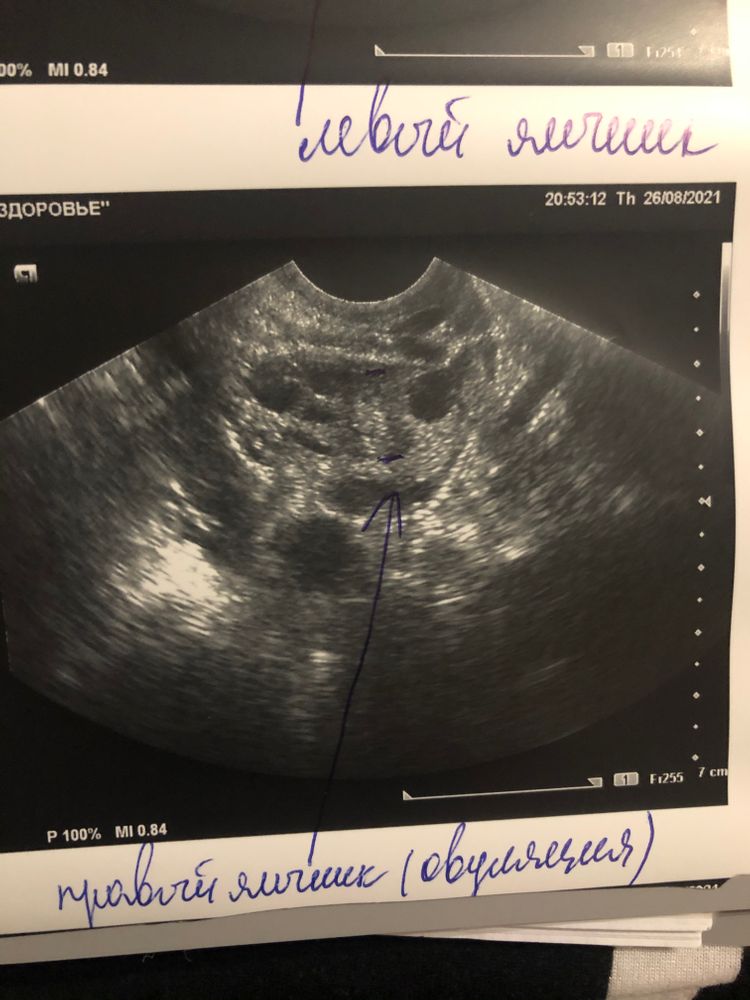

Елена, была на 14дц эт был понедельник, и сегодня 17 дц. Изображение Изображение Изображение

Елена, сказали о была примерно 16-17 дц